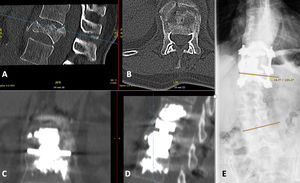

Otro caso implicó a una paciente de 71 años que acudió tras caerse de un caballo, sosteniendo una fractura traumática de T12 (fig. 3). Las radiografías revelaron escoliosis lumbar degenerativa (ángulo de Cobb de 19°). A pesar de tener una puntuación T de -1,9, optamos por fijar el segmento corto con cemento para esta paciente móvil y activa, y debido a los traumatismos axiales recurrentes a causa de la equitación, decidimos realizar la cementación adicional de las placas terminales. El procedimiento se realizó en dos etapas, sin complicaciones. Transcurrido un año postoperatorio, la paciente reportó ser capaz de montar a caballo sin restricciones y, a pesar de la fusión del segmento corto en la unión toracolumbar, el seguimiento más reciente transcurridos cinco años reflejó un resultado clínico y radiológico satisfactorio, sin problema alguno.

Fractura traumática en T12. A/B) TC preoperatoria. C/D) TC postoperatoria tras fijación del segmento corto con tornillos pediculares cementados y VBR con cementación de la placa terminal. E) Rayos X en bipedestación (plano coronal) durante el último seguimiento. La escoliosis lumbar permaneció constante. La paciente fue plenamente funcional, sin limitaciones de la vida diaria transcurridos cinco años postoperatorios.